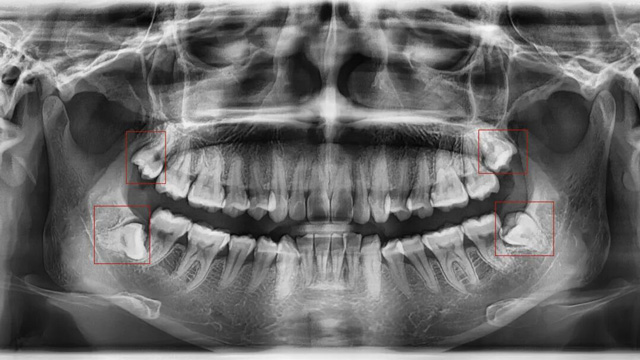

如果通过X光片发现,你的智齿已经顶到邻牙牙根,或者导致邻牙出现龋坏、牙周炎,无论是否正畸,都建议尽早拔除。

有些智齿虽然目前没有疼痛、没有挤压邻牙,但拍X光片后发现,它属于“埋伏阻生”(完全埋在牙龈下),或者生长方向异常,未来很可能会萌出、挤压邻牙,甚至引发囊肿、肿瘤等问题。对于这类堪比“定时炸弹”的智齿,医生通常会建议拔除,避免后续出现更严重的口腔问题。